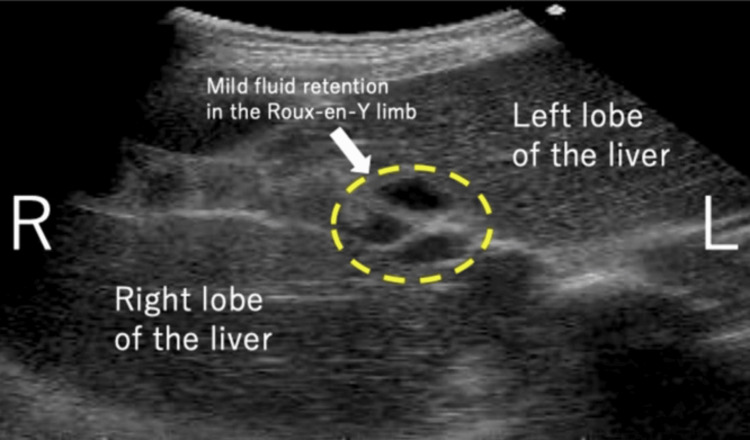

A 35-year-old woman, G1P0, presented with a medical history of CBD. At the age of two, she underwent hepaticojejunostomy with Roux-en-Y reconstruction after resection of the dilated extrahepatic bile duct. She obtained a spontaneous pregnancy and received prenatal care in our hospital from the beginning of the pregnancy. At 35 weeks and one day of gestation, she visited our emergency department due to epigastric pain and recurrent non-bilious vomiting. Her bowel movement was regular and showed normal brown stool. Vital signs were as follows: body temperature 35.8°C, blood pressure 108/76 mmHg, and pulse rate 83 beats per minute. Physical examination revealed spontaneous pain and mild tenderness in the epigastric region, while the abdomen was soft without signs of muscular defense or rebound tenderness. Obstetric examination showed a closed cervix with a cervical length of 30 mm on vaginal ultrasonography. Fetal heart rate monitoring indicated a reassuring fetal status. Blood tests showed a white blood cell count of 11,700/μL, C-reactive protein of 0.08 mg/dL (indicating an absent inflammatory response), and normal liver function with aspartate aminotransferase (AST) 28 IU/L, alanine aminotransferase (ALT) 23 IU/L, and total bilirubin 1.5 mg/dL. Abdominal ultrasonography revealed mild fluid retention in the Roux-en-Y limb at the porta hepatis (Figure 1). An abdominal X-ray, performed to rule out severe intestinal obstruction, showed displacement of the entire intestine due to the pregnant uterus, with partial colonic gas but no obvious signs of niveau formation or distal small bowel gas (Figure 2). Based on these findings, gastroesophageal reflux caused by compression from an enlarged uterus was suspected, and the patient was admitted to our hospital. Because there were limited signs suggesting intestinal obstruction, computed tomography was not performed to avoid unnecessary radiation exposure to the fetus.